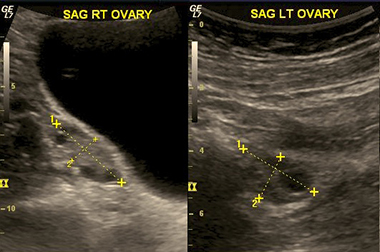

Left and right side ultrasounds of ovaries with developing follicles. |